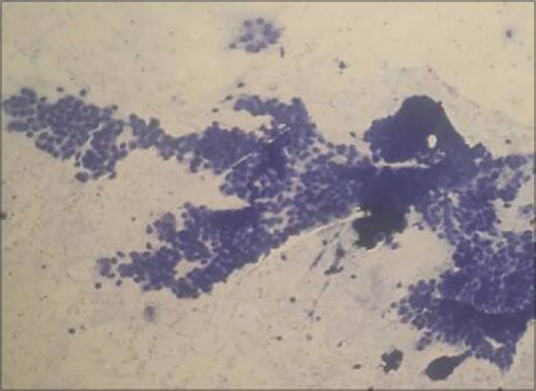

Colloid goiter was the most common diagnosis in benign lesions [Figure 1], followed by Hashimoto's thyroiditis [Figure 2]. The malignant lesions showed follicular neoplasm (4) [Figure 3], papillary carcinoma (2) [Figures [Figures44–6], medullary carcinoma (1) [Figure 7], and anaplastic carcinoma (1) [Figure 8] as shown in Table 2.

| Fig. 2 Photomicrograph of smears from Hashimoto's thyroiditis showing dispersed lymphocytes, tingible body macrophages, and clusters of follicular epithelial cells (Giemsa, ×100)